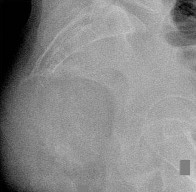

A 15-year-old male presents with deep knee pain awakening him at night. Radiographs show a permeative destructive lesion in the distal femoral metaphysis with a 'sunburst' periosteal reaction and Codman's triangle.

Biopsy confirms high-grade conventional osteosarcoma. What is the most critical prognostic factor for long-term overall survival in this patient?

Explanation

For localized high-grade osteosarcoma, the most important prognostic indicator is the histologic response to neoadjuvant chemotherapy. This is evaluated during the definitive resection. A 'good response' is typically defined as greater than 90% or 99% tumor necrosis. Patients who achieve this level of necrosis have a significantly improved disease-free and overall survival rate compared to 'poor responders' who have extensive viable tumor cells remaining.